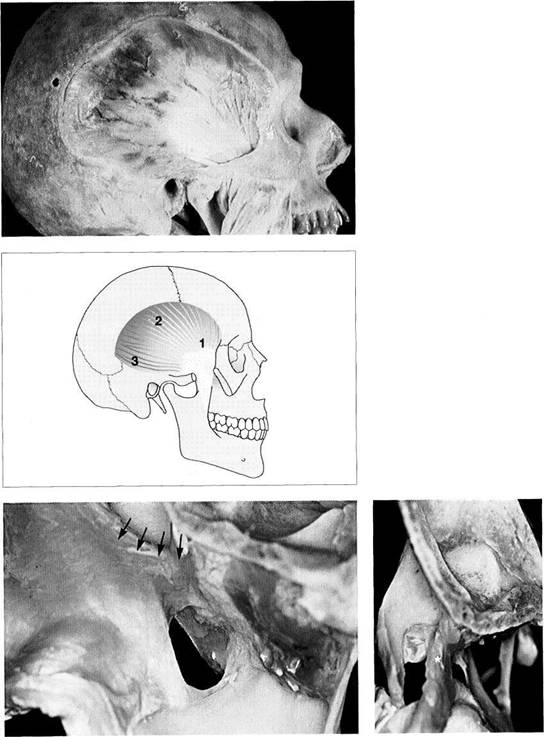

Glenoid Fossa and Articular Protuberance

The temporal portion of the joint can be divided into four functional parts from posterior to anterior: postglenoidal process, glenoid fossa, articular protuberance, and apex of the eminence. The inclination of the protuberance to the occlusal plane varies with age and function (Kazanjian 1940), but is 90% determined at the age of 10 years (Nickel et al. 1988). Three fissures can be found at the transition to the tympanic plate of the temporal bone: the squamotym-panic, petrotympanic, and petrosquamous fissures (Fig. 28). In patients with disk displacement, these fissures are fre-

quently ossified (Bumann et al. 1991). Under physiological conditions the only parts of the temporal portion of the joint that are covered with secondary cartilage are the protuberance and the eminence (Fig. 31). Secondary cartilage is formed only when there is functional loading. Before the fourth postnatal year stimulation of the cells of the perio-seum leads to the formation of secondary cartilage (Hall 1979, Thorogood 1979, Nickel et al. 1997). With no persisting functional load the chondrocytes of the condyle would differentiate into osteoblasts (Kantomaa and Hall 1991).

Joint

region of the temporal

bone

Inferior view of the temporal portion of a defleshed temporomandibular joint. Near the upper border of the picture is the articular eminence (1) and at the far left is the external auditory meatus (2). In the posterior portion of the fossa the squamotympanic fissure (3) is found laterally, and the petrosquamous (4) and petrotympanic (5) fissures are found medially. Both the superior stratum of the bilaminar zone and the posterior portion of the joint capsule, and sometimes also the fascia of the parotid gland can insert into these fissures.

Ossification

of the fissures

and disk displacement

Inferior view of a temporal bone with partially ossified fissures. The lateral half of the squamotympanic fissure is completely ossified (arrows). The superior stratum of the bilaminar zone can now insert only into the periosteum in this region. It has been shown that these fissures are ossified in more than 95% of patients with disk displacement, whereas in joints without disk displacement normal fissure formation prevails (Bumann et al. 1991).

Inferior view of the temporal cartilaginous joint surface and capsule attachment

Caudal view of the left temporomandibular joint of a newborn. The bony portions have been separated from the periosteum up to the circular insertion of the capsule and bilaminar zone. Part of the zygomatic arch (1) can be seen near the right border of the photograph. The fibrocartilaginous articular surfaces over the articular protuberance are thickened medially and laterally (arrows). When covered with synovial fluid they allow movements with virtually no friction (Smith 1982).

Sagittal

histological section

showing buildup of the temporal

joint components

The temporal portion of the joint can be divided into four functional components: 1 postglenoidal process, 2 glenoid fossa, 3 articular protuberance, and 4 apex of the eminence. As a rule, no cartilage can be identified within the fossa. The average thickness of the fibrous cartilage over the protuberance and the eminence is between 0.07 and 0.5 mm (Hansson et al. 1977). As this photograph shows, there can be considerable variation in thickness within the same individual.